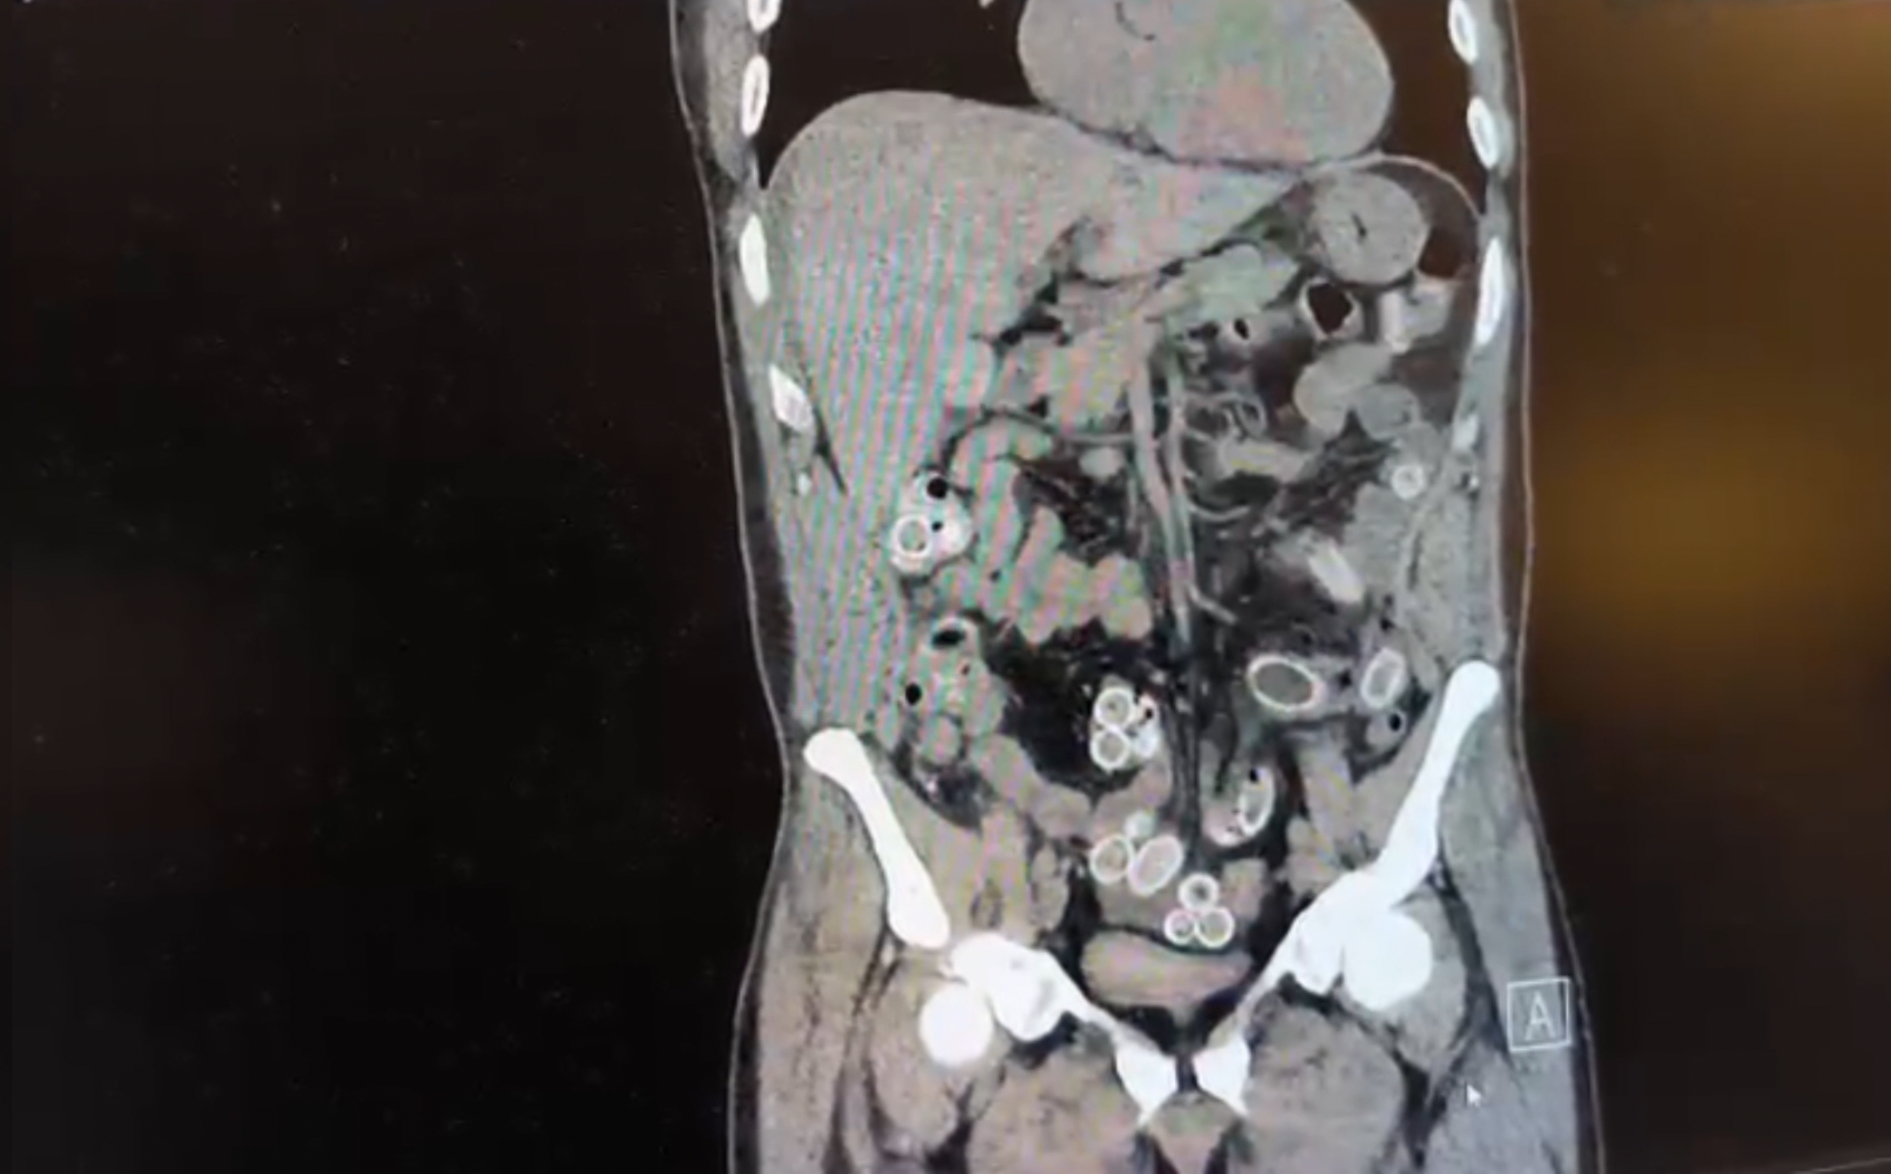

Fas'tan Türkiye'ye gelen Cüneyt Ç., mide ağrısı şikayetiyle hastaneye gitti. Midesinden onlarca esrar kapsülü çıkarılan şüpheli taburcu edildikten sonra tutuklandı.